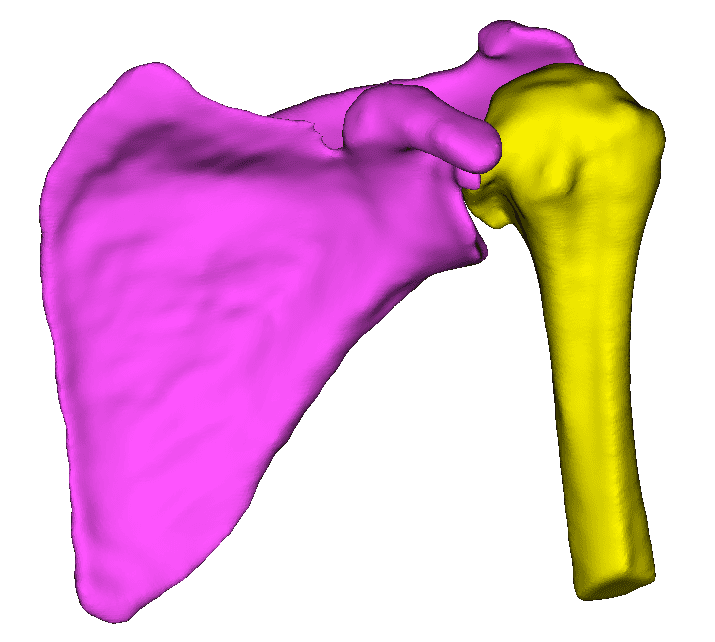

Real-time 3D rendering of segmented structures. Create patient-specific anatomical models for visualization and analysis.

Quickly visualize and analyze anatomical structures from CT and MRI scans. Identify abnormalities with precise 3D visualization.

Create patient-specific 3D anatomical models for pre-operative planning. Enhance surgical precision and patient outcomes.